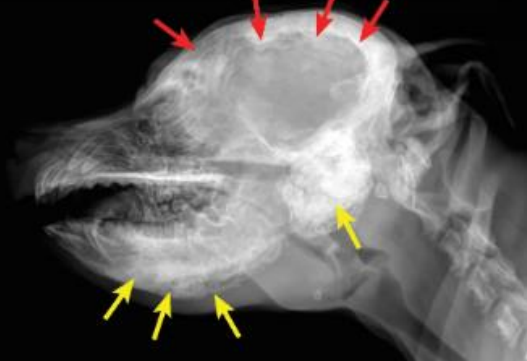

![]() ![]() | - caudal mandibles์ irrecular bone density๊ฐ ์ฆ๊ฐ. - tympanic bullae์ ๋ฐ๋๋ ์ฆ๊ฐ. - 1/3์ ํ์๋ mandible์ ๊ตญํ๋ ๋ณ๋ณ์ ๋ณด์ด์ง๋ง, ์ผ๋ถ ๊ฒฝ์ฐ skull์ ๋ฐ๋ฅ์ ๋ณ๋ณ, ๋๋ ๋๊ฐ๊ณจ ์์ฒด๊ฐ ๋น๋(thickened calvarium). - ๊ฐ๊ฐ ์ฑ์ํด ๊ฐ๋ฉด์, ์๋ก์ด ๋ผ์ ๊ฐ์ฅ์๋ฆฌ๊ฐ ๋งค๋๋ฌ์์ง๊ณ , ๋น์ ์ ๋ถ์๊ฐ ์ค์ด๋ฆ. |

![]() | - mandible ์ชฝ ๊ฒฝ๊ณ๊ฐ ๋ฌด๋์ ธ ์์. - skull ๋ค์ชฝ์ด ํ์ฐํ ๋๊บผ์์ ธ ์์. |

![]() | - tympanic bullae๊ฐ ์ ๋ณด์ผ ์ ๋๋ก ๋๊บผ์์ ธ ์์. |